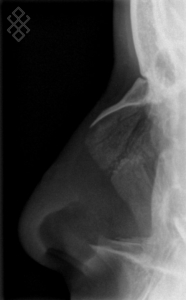

Radiographie des Os Propres du Nez (OPN)

Pour une radiographie des os propres du nez, aucune préparation n'est requise. Il est recommandé d'enlever tous les bijoux avant de se présenter.

Vous serez installés en position debout.

La durée de l'examen est d'environ 5 minutes.

Après la fin de la radiographie des os propres du nez, vous pourrez continuer vos activités de la journée sans problème. S'il y a eu une injection, le manipulateur en radiologie retirera le cathéter et il vous sera recommandé de boire beaucoup d'eau afin d'éliminer au mieux le produit de contraste.

Avant de passer une radiographie des os propres du nez (OPN), il est primordial de signaler si vous êtes ou pensez être enceinte. En effet, vous devrez passer l'examen sous certaines conditions.